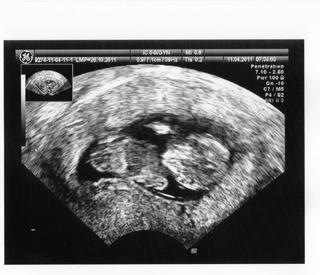

Ahojte 🙂 Tak sme doma 🙂 NT screening dopadol výborne, NT meranie 1mm 😉 Zajtra ideme do poradne tak budeme vedieť ostatné výsledky krvi atď. Podľa UTZ zodpovedáme 12tt+0, malá piškótka krásne rastie máme už 53mm a všetko je v úplnom poriadku. Hematóm zmizol takže sme čistý 😉 Maličké bolo dosť lenivé, nechcelo sa fotiť, ale tak nakoniec aby sa nepovedalo tak nám ukázal ako sa vie poškrabať rúčkou po hlavičke viď foto 😉 😉 😉